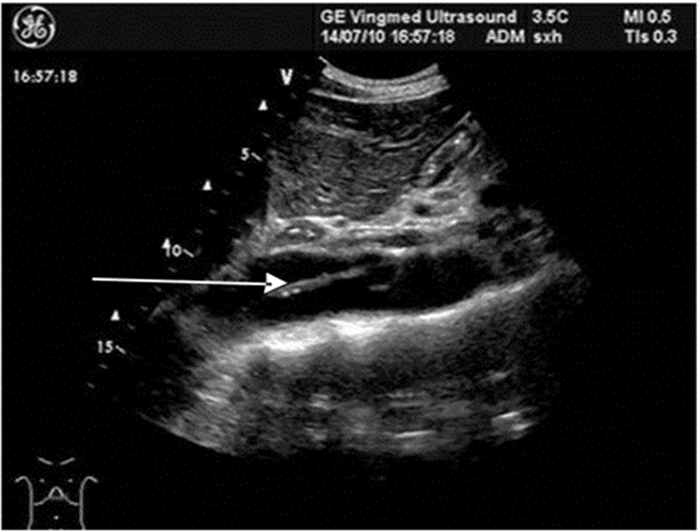

升主动脉根部直径>40 mm或腹主动脉内径>25 mm提示主动脉扩张,常见于主动脉瘤、急性主动脉综合征、高心病、主动脉瓣关闭不全、马方综合征等。主动脉被撕脱内膜(动脉腔内带状较强回声)分为真、假两腔(图 18),此时可考虑主动脉夹层。

| 图 18 箭头所示为撕脱的腹主动脉内膜 |